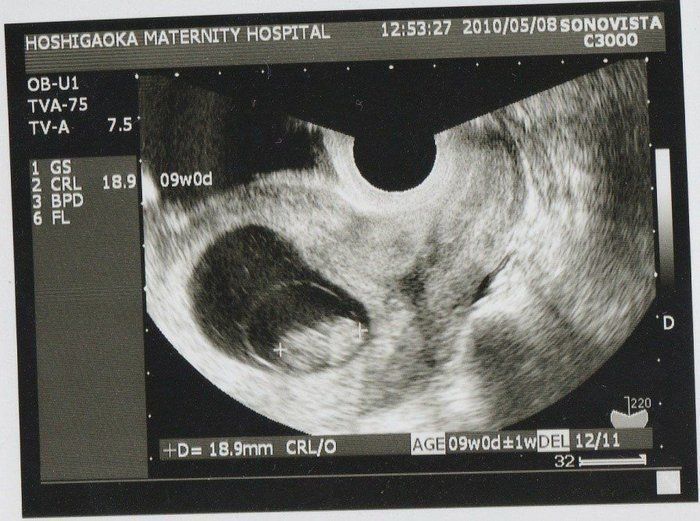

Amiさんの妊娠9週目のエコー写真

この写真から、胎嚢の中の我が子が二頭身になっていることがわかります。赤ちゃんの大きさは18.9mm。ちょうど枝豆一粒くらいの大きさですが、この時期は胎芽から胎児へ移行する時期のようです。それほど体調に変化もなく、「本当に自分のおなかに赤ちゃんがいるのか」と不思議な気持ちでした。